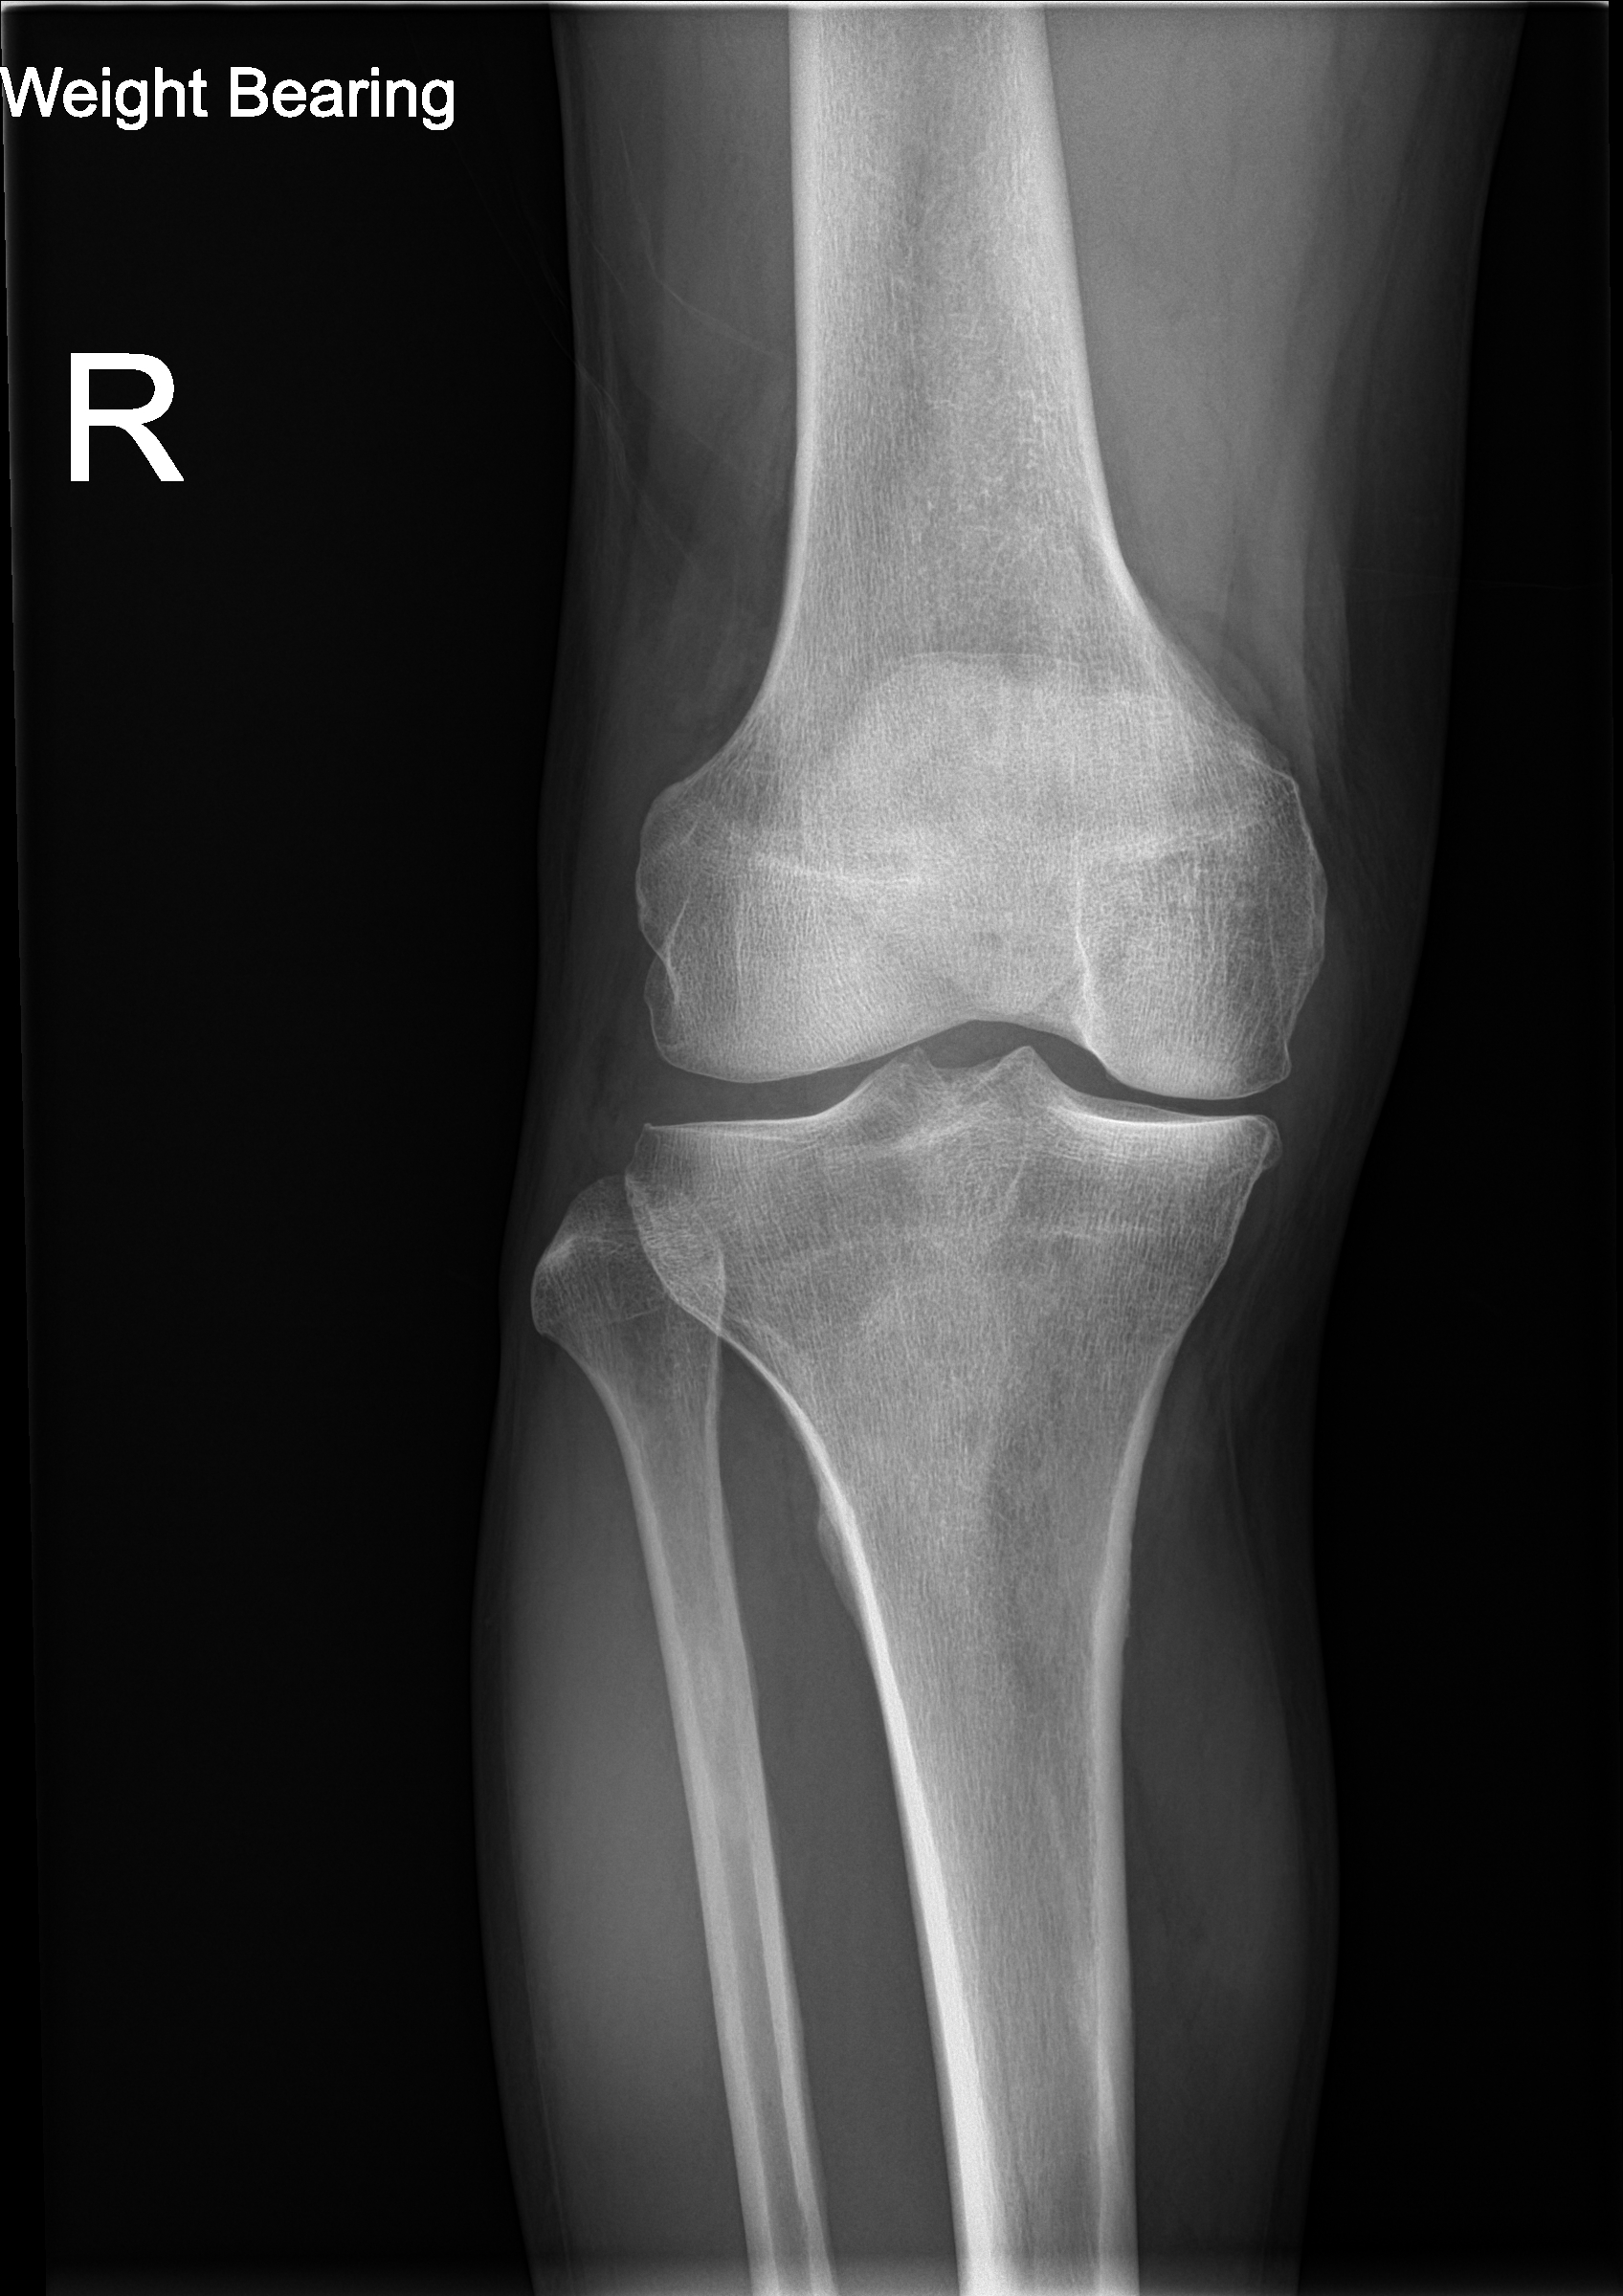

Normal knee phantom with intact bone, cartilage, menisci, and ligaments for baseline comparison